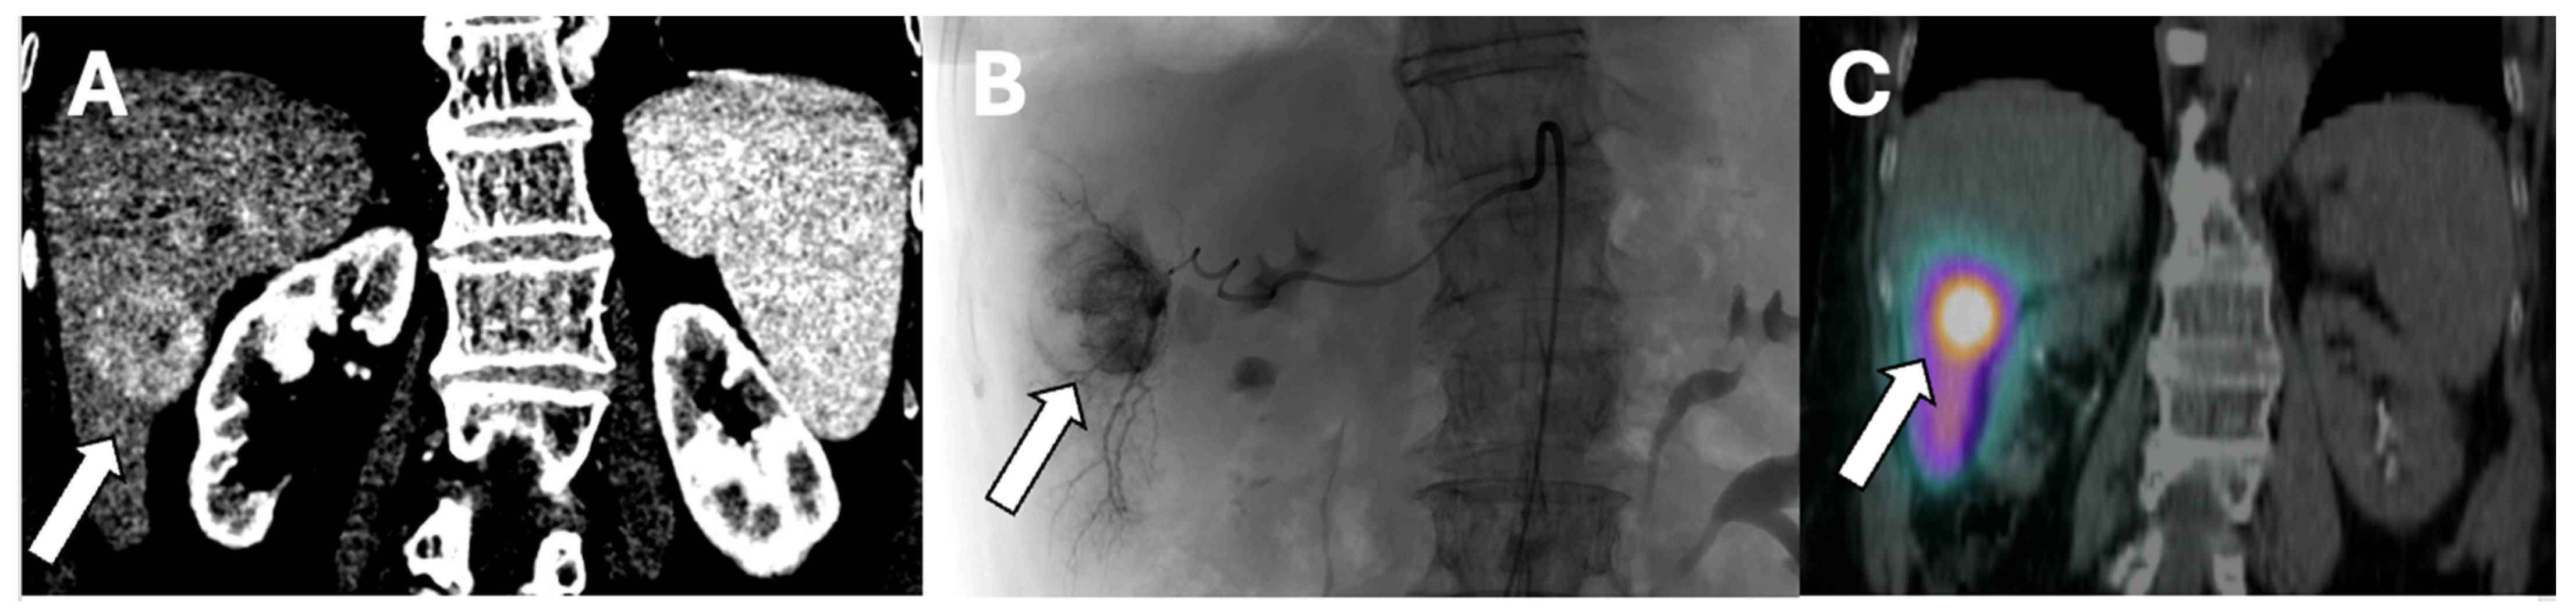

SIRT can be applied selectively to one or two segments of the liver or to an entire lobe. Segmental administration or radio-segmentectomy is performed with a higher dose to ablate the treated area, while lobar administration is performed with a lower dose intending to arrest tumor growth and induce hypertrophy of the remaining liver segments. This distinction is important when planning SIRT treatments [32]. Figure 1 is an example of Y-90 radiation segmentectomy treatment.